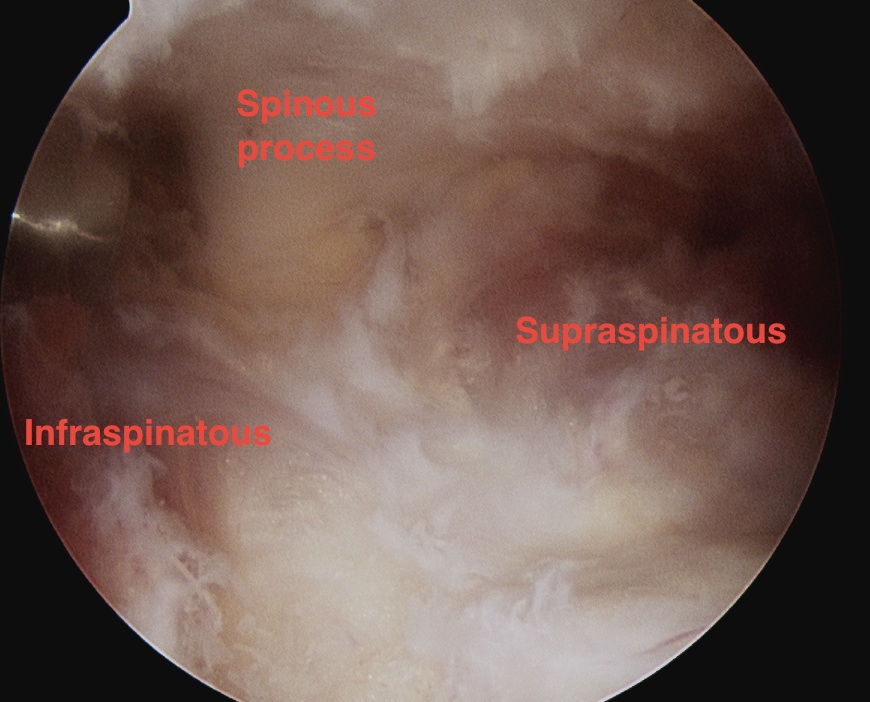

Subacromial space approach

Ghodadra et al Arthroscopy 2009

- subacromial space

- identify spine of scapula and dissect between infraspinatous and supraspinatous

- accessory posterior portal, retract IS and nerve

- decompress with shaver

Subacromial space approach to cyst decompression